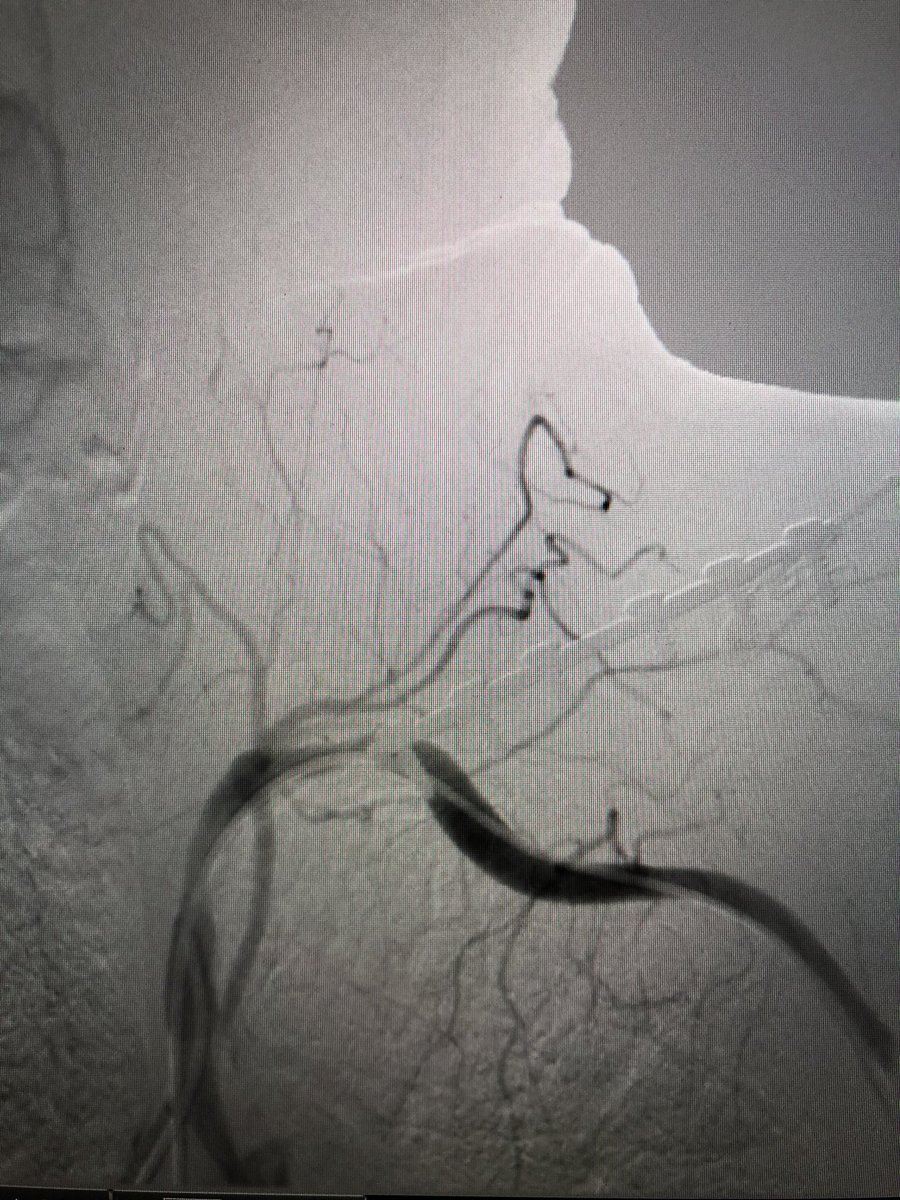

Hard to fully appreciate on still image. Selective angiography images included -R CCA stenosis and R ICA occlusion -aberrant R SCA (Arteria Lusoria) occluded after the R vertebral origin - moderate L SCA disease with L vertebral occlusion #SCAIPAD #ACCFIT #RadialFirst

-R CCA stenosis and R ICA occlusion

-aberrant R SCA (Arteria Lusoria) occluded after the R vertebral origin

- moderate L SCA disease with L vertebral occlusion